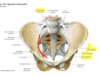

- lig inguinale

- SIAS

- tuberculum pubicum

- lig sacroiliaca anteriora